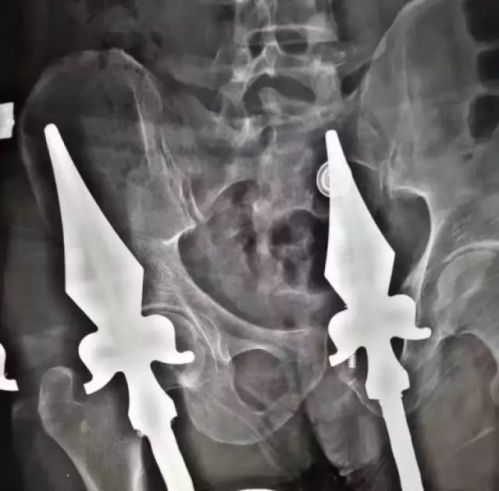

中队到场发现,一名男子在安装空调时不慎从二楼跌落,呈坐姿卡到栅栏上,臀部插入了两根钢筋,消防官兵和120医护人员商讨后,立即对栅栏展开切割破拆,随后,紧急送往医院救治。

消防员用破拆工具将栅栏剪断,将男子放到地面上,期间男子难忍剧痛,不断大叫。

医院其后为男子动手术,取出插入体内的栅栏,目前其情况已转危为安。